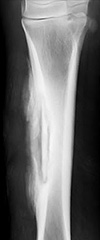

• 四肢、肋骨の骨折や腐骨、関節炎といった運動器外科

• 腐骨形成